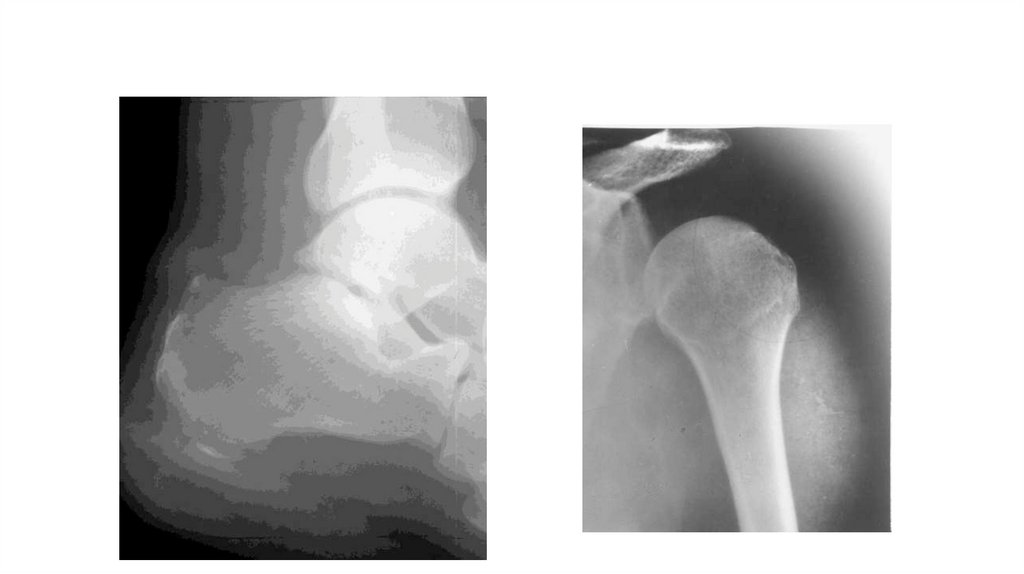

Воспалительные заболевания опорнодвигательного аппарата

«Воспалительные

заболевания опорнодвигательного аппарата»